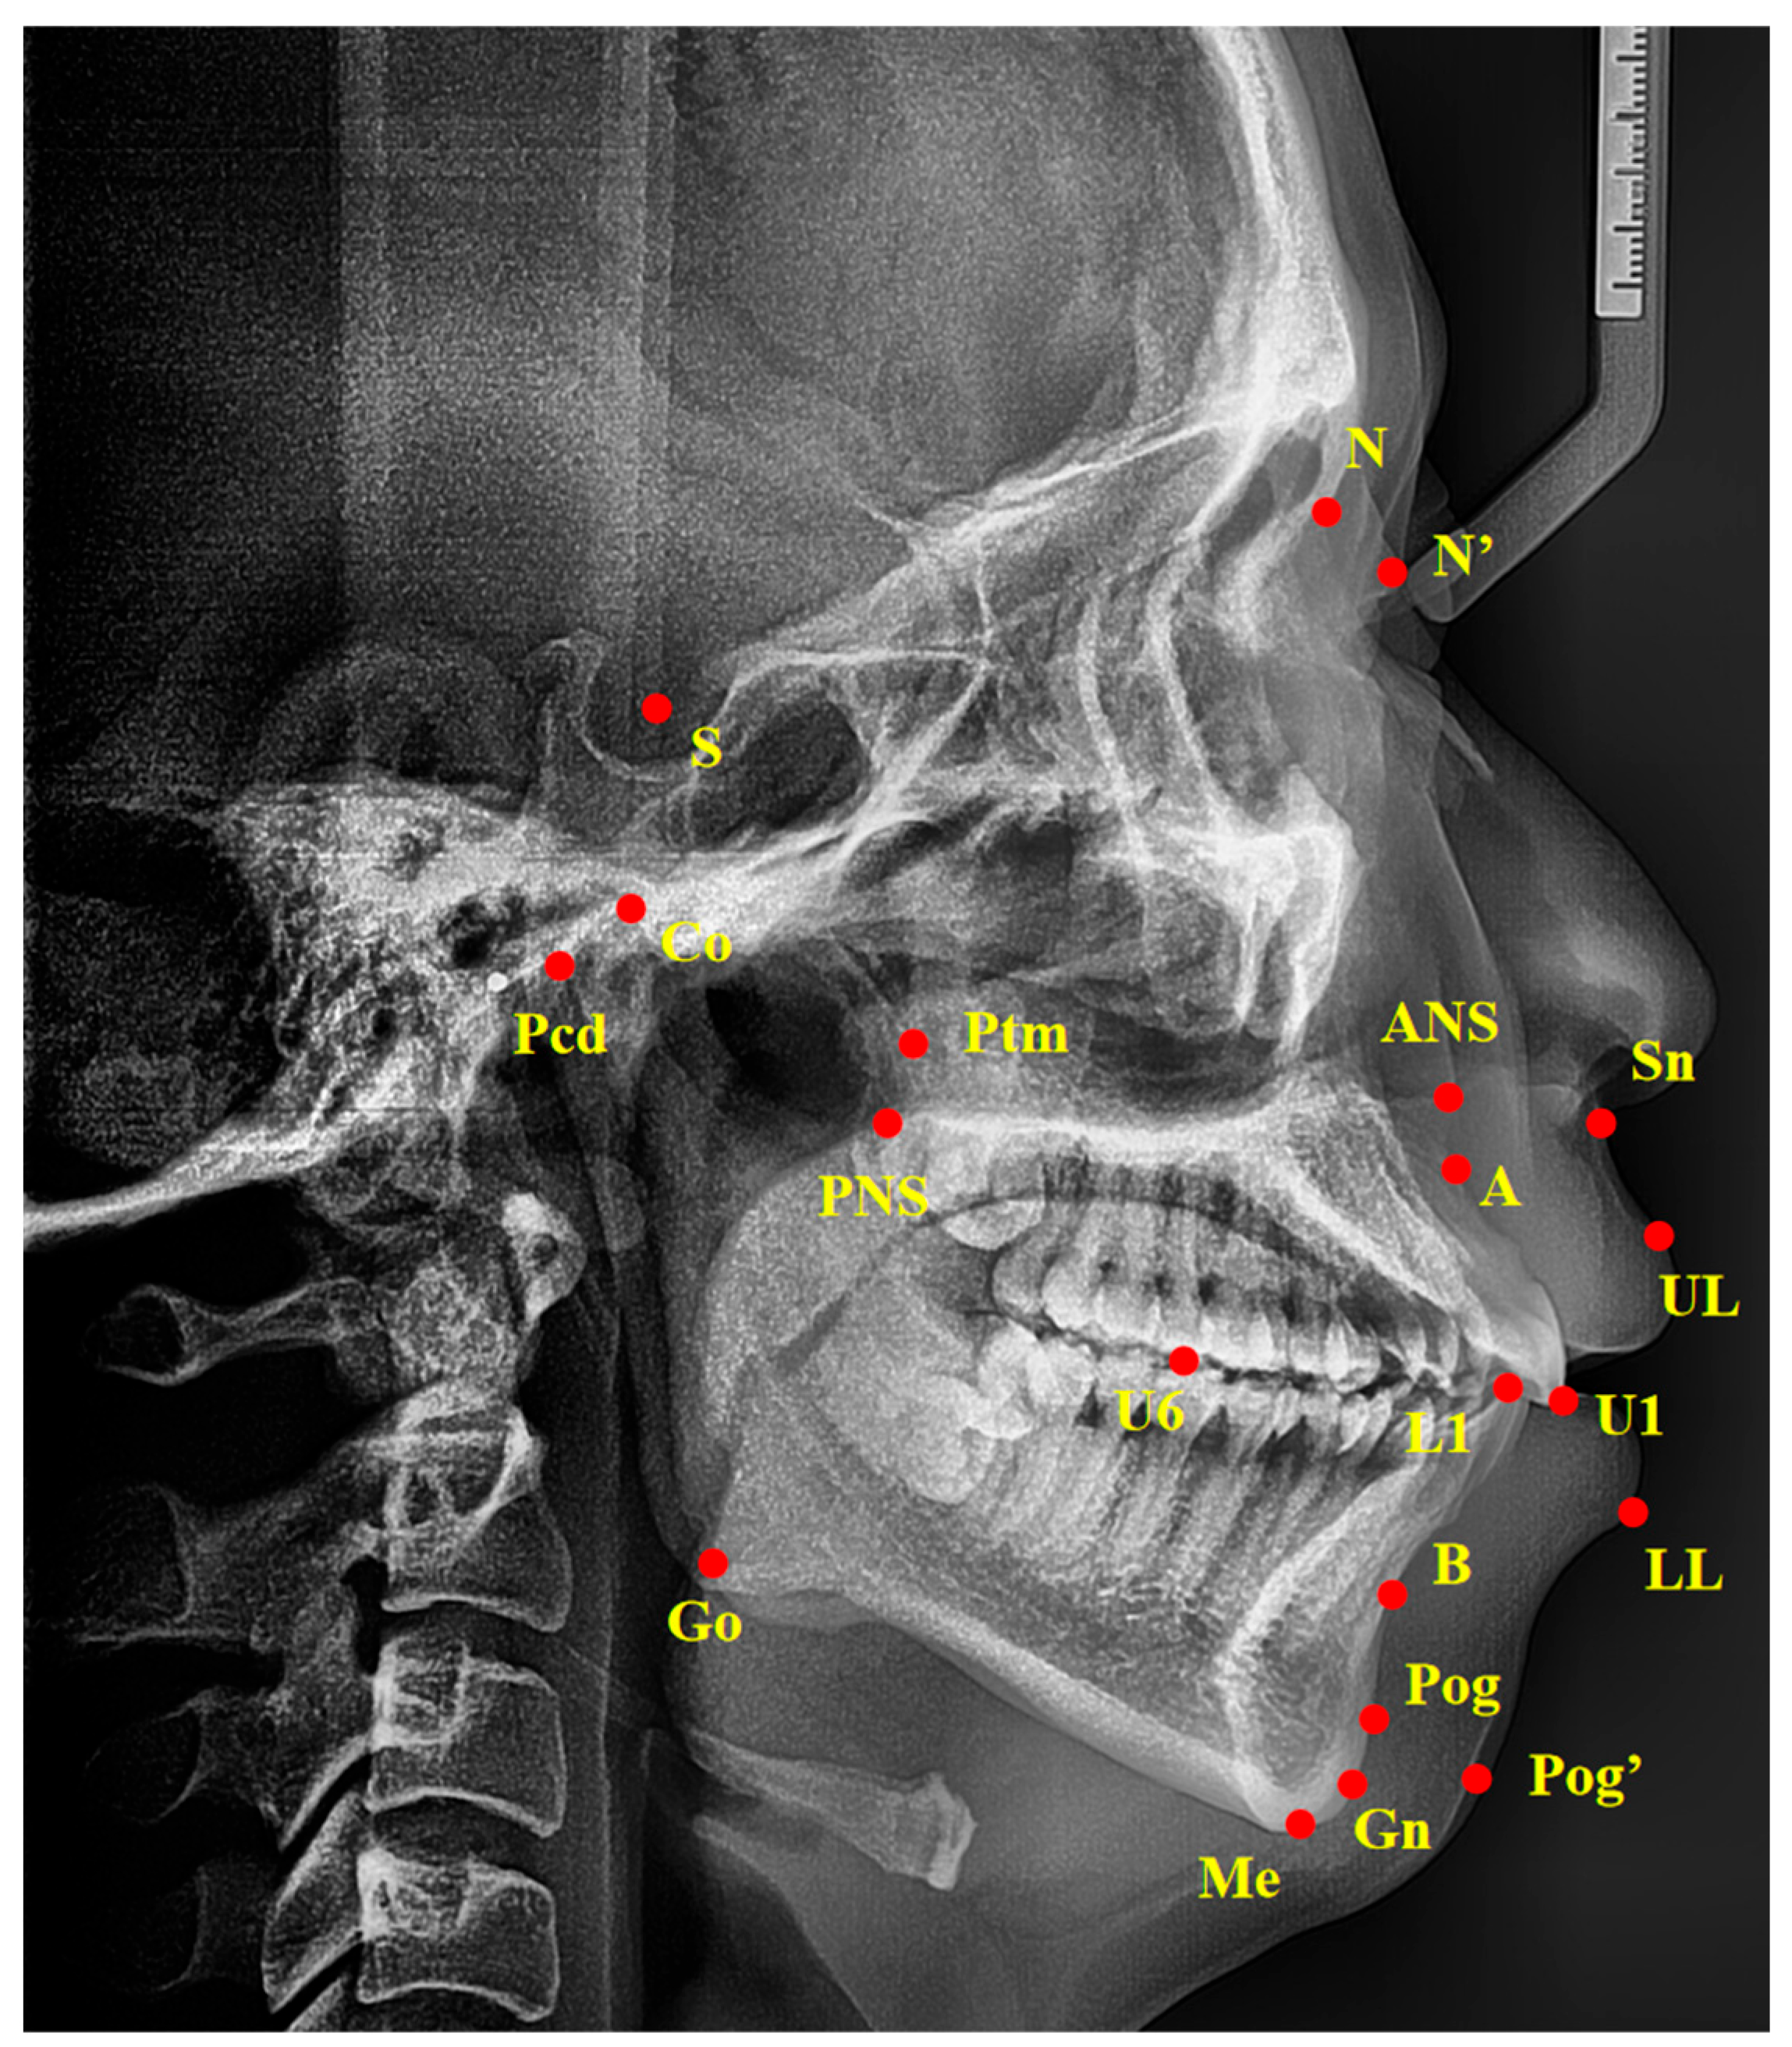

2.3. Cephalometric Analysis

| Measurements | Description |

|---|---|

| Angular measurements (°) | |

| SNA | Angle between point S and A at N |

| SNB | Angle between point S and B at N |

| ANB | Angle between point A and B at N |

| PP-FH | Angle between PP plane and FH plane |

| PP-GoGn | Angle between PP plane and line Go–Gn |

| OP-SN | Angle between occlusal plane and SN plane |

| MP-SN | Angle between mandibular plane and SN plane |

| FH-MP | Angle between FH plane and mandibular plane |

| SGn-FH | Angle between line S–Gn and FH plane |

| NBa-PtGn | Angle between line N–Ba and line Pt–Gn |

| U1-L1 | Angle between the long axis of upper incisors and lower incisors |

| U1-SN | Angle between the long axis of upper incisors and SN plane |

| U1-NA | Angle between the long axis of upper incisors and line N–A |

| L1-NB | Angle between the long axis of lower incisors and line N–B |

| L1-FH | Angle between the long axis of lower incisors and FH plane |

| Z-Angle | Angle between line Z-line and FH plane |

| FH-N’Pog’ | Angle between FH plane and line N’Pog’ |

| N’-Sn-Pog’ | Angle between point N’ and Pog’ at Sn |

| Linear measurements (mm) | |

| Ptm-A | Distance between Ptm and A |

| Ptm-S | Distance between Ptm and S |

| Go-Pog | Distance between Go and Pog |

| Go-Co | Distance between Go and Co |

| Pcd-S | Distance between Pcd and S |

| N-ANS | Distance between N and ANS |

| ANS-Me | Distance between ANS and Me |

| S-Go | Distance between S and Go |

| U1-NA | Distance between U1 and line N–A |

| L1-NB | Distance between L1 and line N–B |

| U1-APo | Distance between U1 and line A–Pog |

| L1-APo | Distance between L1 and line A–Pog |

| U6-Ptm | Distance between U6 and Ptm |

| U1-PP | Distance between U1 and PP plane |

| U6-PP | Distance between U6 and PP plane |

| L1-MP | Distance between L1 and mandibular plane |

| L6-MP | Distance between L6 and mandibular plane |

| UL-EP | Distance between UL and EP plane |

| LL-EP | Distance between LL and EP plane |